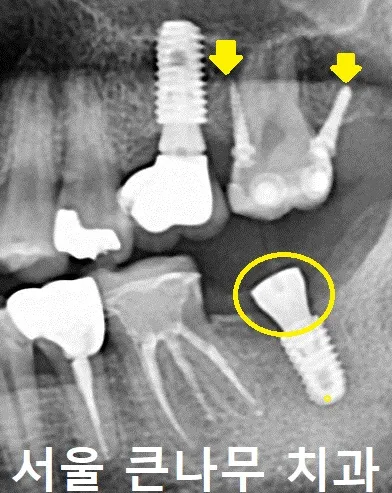

아래 심어놓은 임플란트는 뼈와 잘 유착이 되었습니다. 간단한 수술 후 잇몸 위로 올라오는 나사(Healing Abutment)로 교체해 주었습니다.

한 달 뒤 임플란트는 최종 보철을 끼워 완료하였습니다.

최종 보철이 장착된 모습입니다.

사진에서 임플란트 가운데 보이는 구멍은 나사와 연결된 구멍으로 수리할 일에 대비하여 나사를 조였다 풀었다 하기 위해 만든 것입니다. 평소에는 저렇게 치아색이 나는 레진으로 단단하게 메꿔주어 빠지지 않게 사용합니다.

4개월 차

생각보다 부분 교정이 빨리 진행되어 4개월차에 마무리하게 되었습니다. 위에 달려있던 장치와 나사 모두 제거하였고, 4개월 만에 안정적인 상태로 자리 잡을 수 있게 되었습니다.